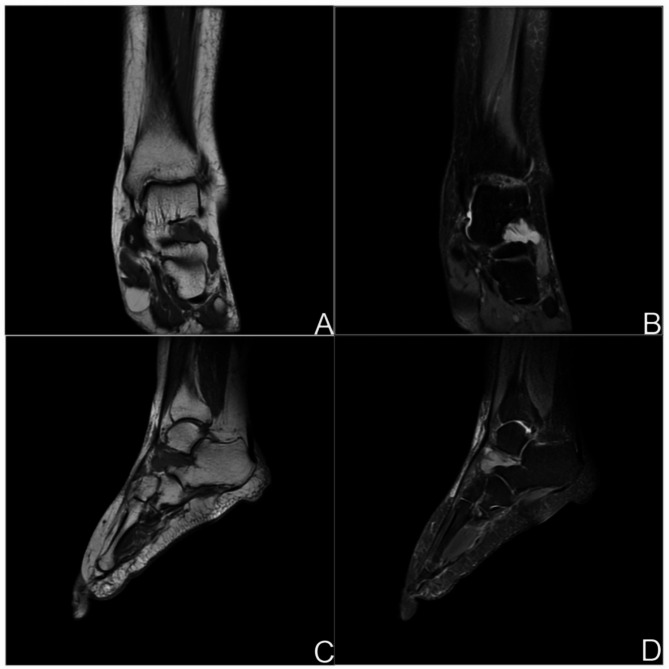

Case presentation: A 48-year-old Chinese woman presented with a 3-year history of recurrent pain and limited mobility in her left ankle. She had previously been misdiagnosed with conditions such as ankle sprain, synovitis, or tarsal sinus syndrome. After undergoing arthroscopic synovectomy, pathological examination confirmed the diagnosis of synovial sarcoma.